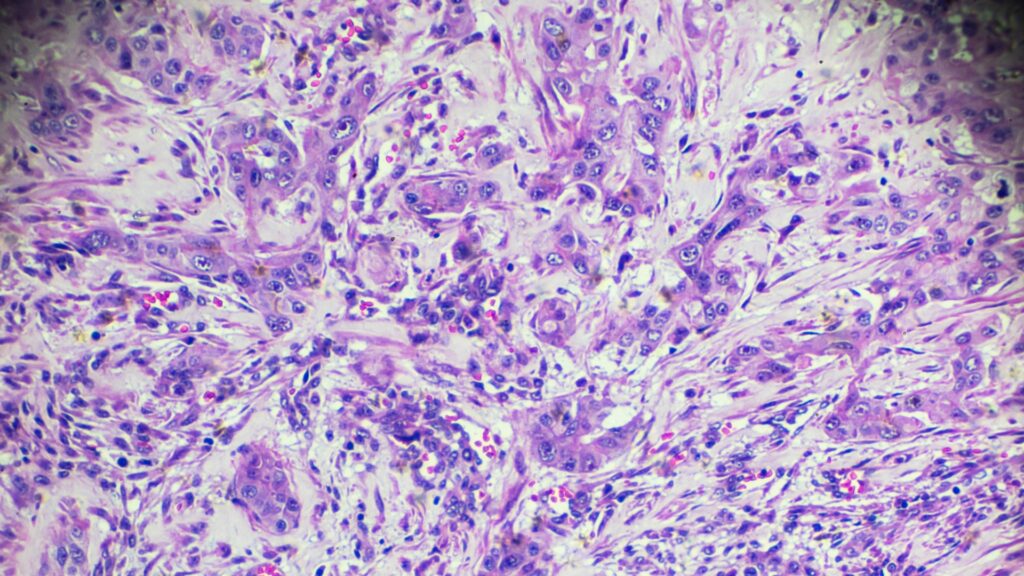

O Carcinoma Hepatocelular é o tumor maligno primário mais comum do fígado e a terceira principal causa de morte por câncer no mundo. Diferente de outras neoplasias, geralmente surge em um “solo fértil”: o fígado cirrótico. O manejo deste paciente exige um equilíbrio delicado entre tratar o câncer epreservar a função hepática restante.

A regra prática é clara: 90% dos casos de CHC ocorrem em pacientes cirróticos. A inflamação crônica e a regeneração nodular incessante criam o ambiente propício para mutações.

- Hepatite B (HBV): Possui um mecanismo de carcinogênese único. O vírus B integra seu DNA ao genoma do hepatócito, podendo causar CHC mesmo na ausência de cirrose.